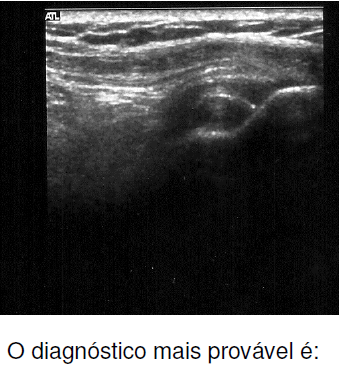

Paciente de 60 anos de idade com dores persistentes no ombro esquerdo há três meses, refratárias ao tratamento conservador. O exame de USG revela tendão supraespinal hipoecoico e linha hiperecoica na inserção, conforme a imagem abaixo.